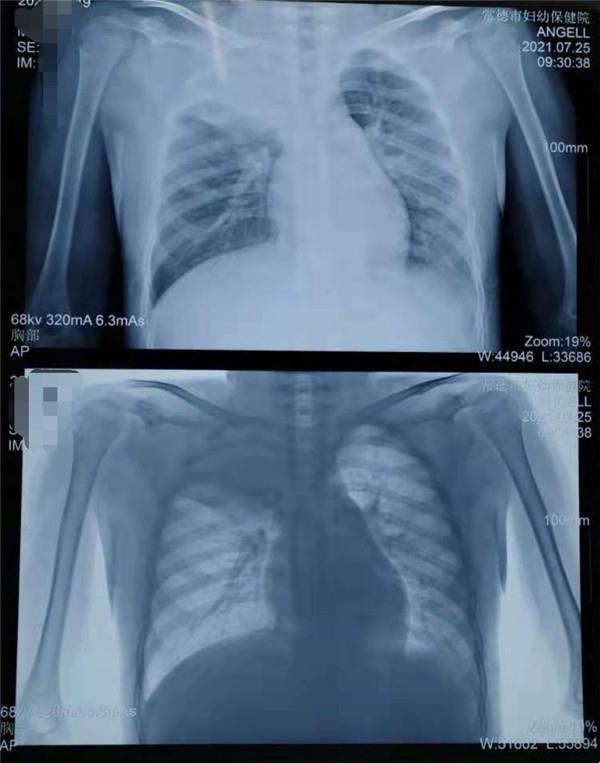

胸部X片:右上肺及左下肺大片高密度影